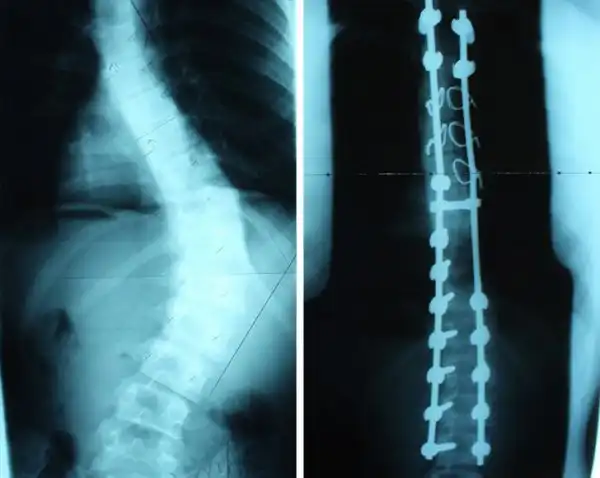

Рентгеновский снимок до и после операции исправлению сколиоза